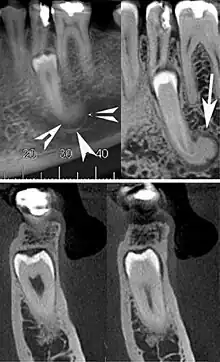

| Cone beam CT images showing a well-defined hyperdense round lesion attached to the root of supernumerary mandibular tooth (arrow head) with a surrounding hypodense rim.[1] | |

A cementoblastoma in a radiograph appears as a well-defined, markedly radiopaque mass, with a radiolucent peripheral line, which overlies and obliterates the tooth root. It is described as having a rounded or sunburst appearance. There is usually apparent external resorption of the root where the tumor and the root join. Severe hypercementosis and chronic focal sclerosing osteomyelitis are lesions to consider in the differential diagnosis of this lesion.